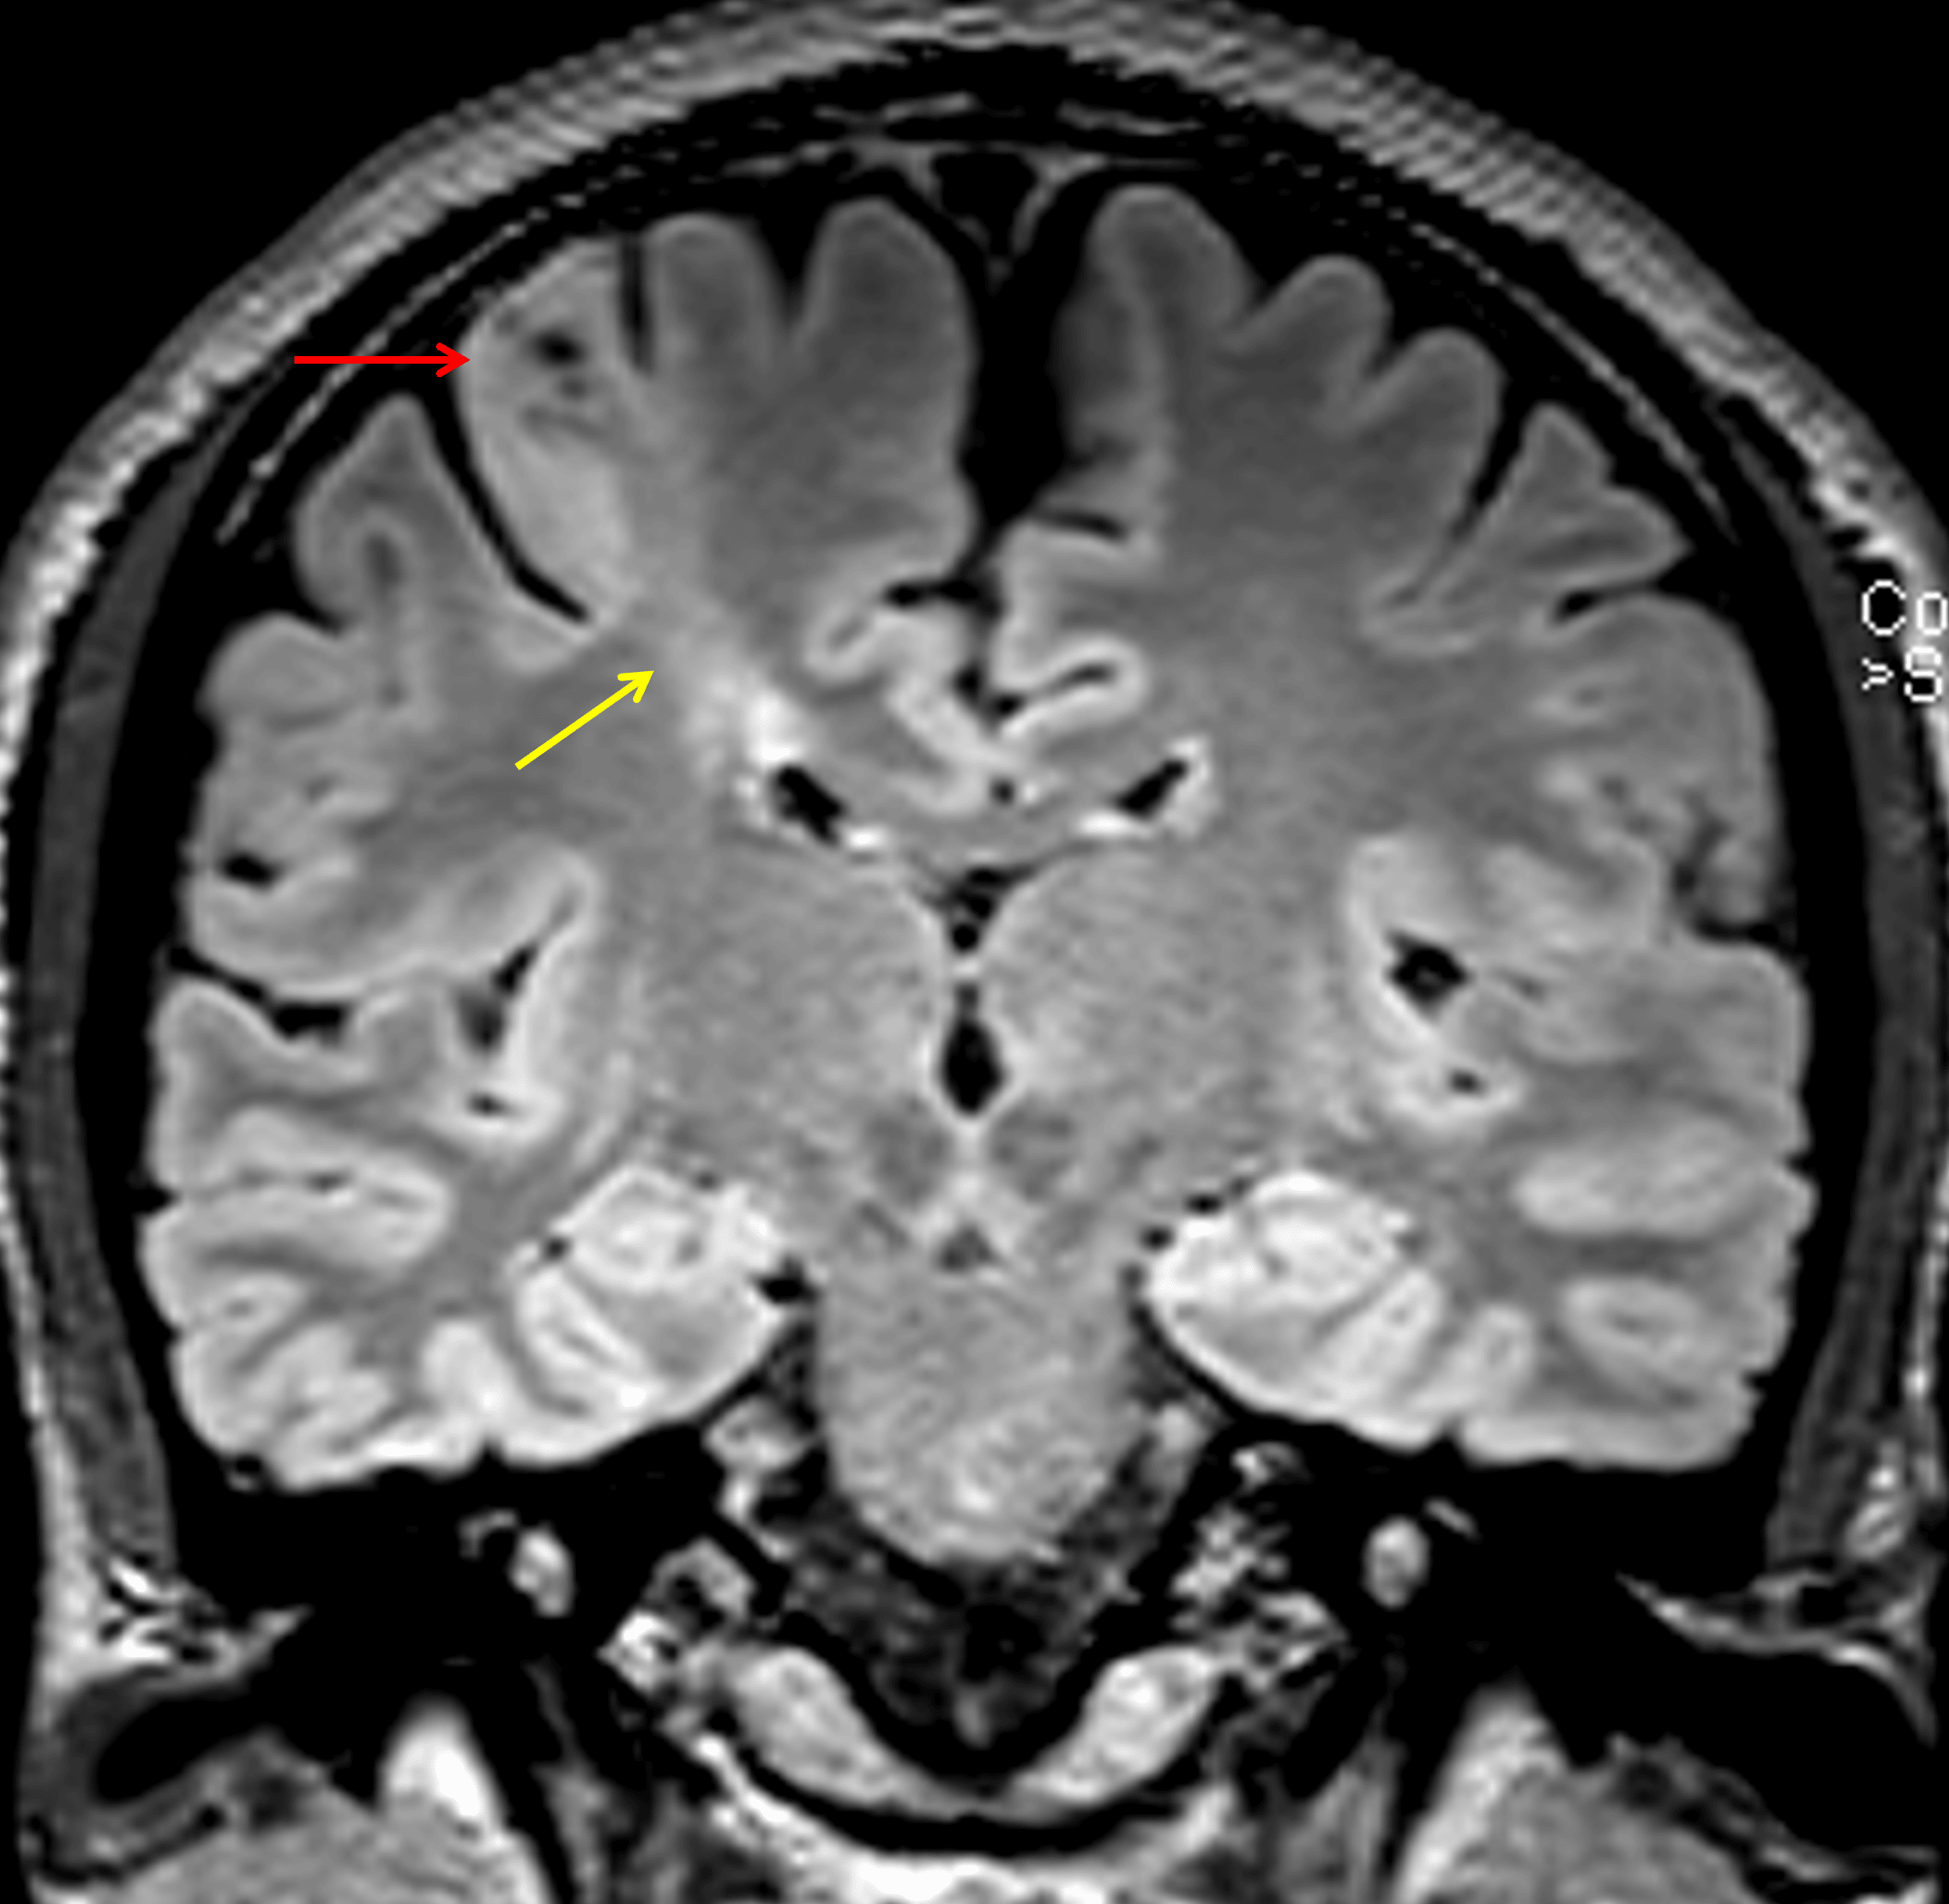

• T2/FLAIR signal hyperintensity in the right precentral gyrus (including the hand motor knob) and extending slightly into the postcentral gyrus with blurring of the gray-white interface

• Band of T2/FLAIR signal hyperintensity bridging this abnormal cortex and the ventricular ependymal margin

• No substantial gyral expansion or intracranial mass effect

Abnormal cortical thickening and T2/FLAIR signal hyperintensity (red arrow) with blurring of the gray-white junction and a band of T2/FLAIR signal hyperintensity extending to the underlying ventricular margin (yellow arrow).